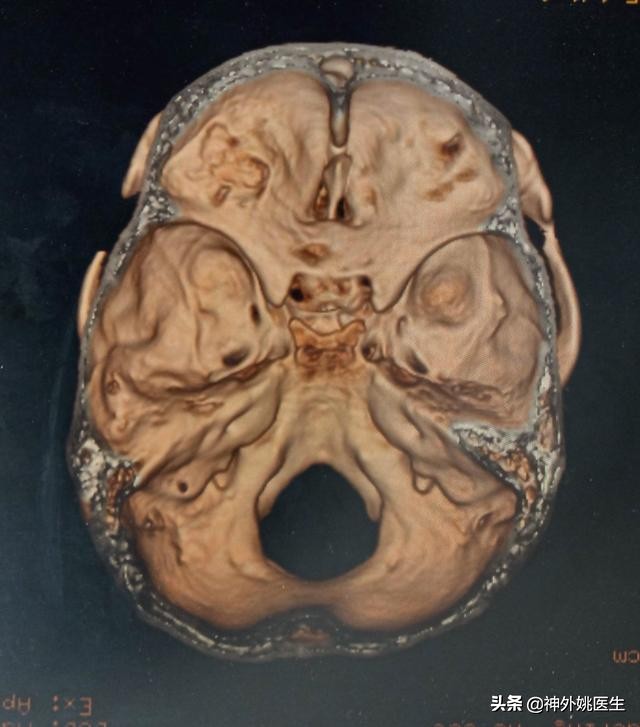

头CT检查:左额部占位,考虑脑膜瘤。(图1、2)

图2 左前颅底骨质凹凸不平,未见骨质明显破坏。